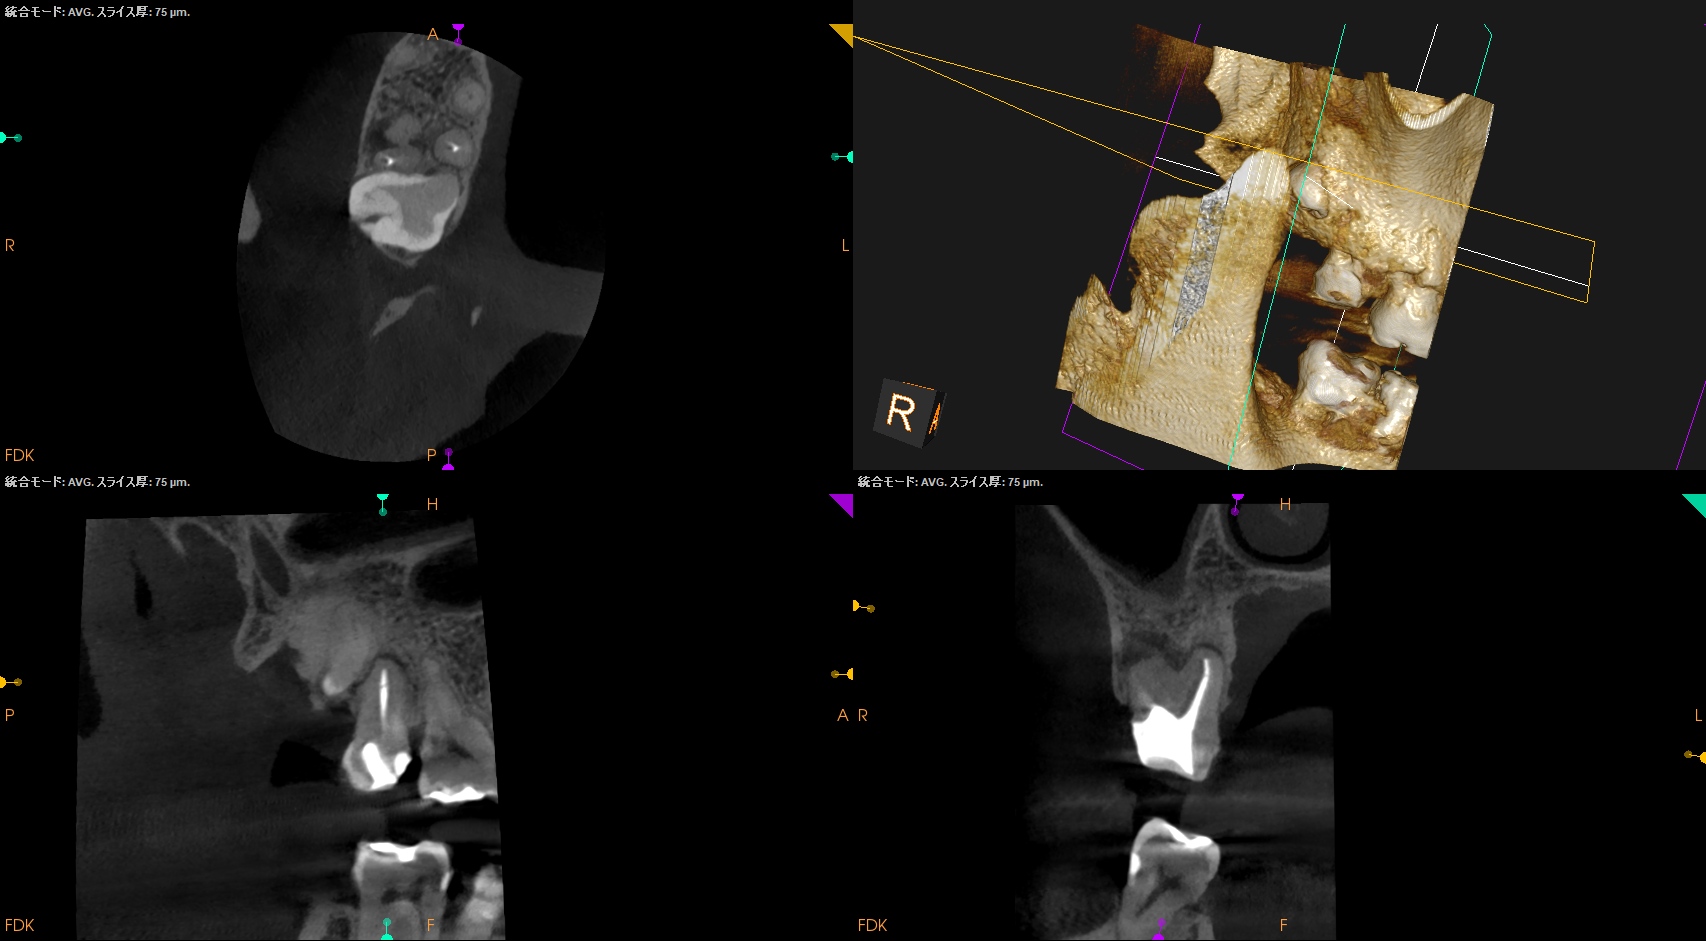

Pre-op Endo test(2025.12.12)

#2 Cold N/A, Perc.(+), Palp.(-), BT(++), Perio Probe(WNL), Mobility(WNL)

依頼された#2には咬合痛と打診痛がある。

近心根にファイルが折れ込んでいる。

MB

DB

P

Pre-op Endo Diagnosis(2025.12.12)

Pulp Dx:Previously treated

Periapical Dx:Symptomatic apical periodontitis

Recommended Tx: Intentional Replantation